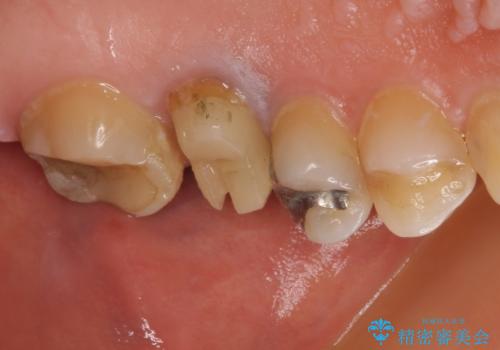

- 近医にて抜歯が必要と診断されたとのことで来院された患者様です。

術前の診査では、歯が破折している可能性が高いものの、確実に抜歯が必要と診断ができない状態でした。

状況次第では抜歯が必要となり、その際にはインプラント治療を行うことを了承いただいた上で、破折していない場合には根管治療を行うこととしました。

土台の材料を外して顕微鏡下で確認したところ、歯根にまで及ぶ破折が認められたため、インプラント治療を行うこととしました。

他にも銀歯や欠損となっている歯に対しての治療も希望されたため、補綴治療を行うこととしました。